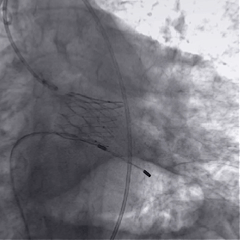

术中影像

根部造影

球囊预扩

瓣膜稳定释放

瓣膜展开后造影

再次造影,确认瓣膜位置

稳定脱钩

最终造影,瓣膜位置良好,无明显瓣周漏

外周血管检查